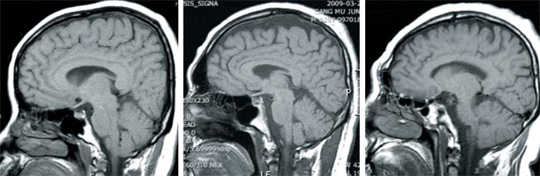

↑ [조선일보]정상적인 30대 중반 남성의 뇌(사진 왼쪽), 10년간 술마신 28세 남성… 정상 뇌보다 20% 수축(사진 가운데), 노화로 수축된 65세 남성의 뇌(사진 오른쪽).

일종의 '알코올성 치매'라는 판정을 받은 것이다. 담당 의사가 김씨의 뇌 MRI(자기공명영상) 사진과 평범한 30대 정상인의 뇌 MRI 사진을 동시에 모니터에 띄워놓고는, "당신의 뇌는 현재 70대 노인에게서나 발견되는 뇌 위축 상태"라며 "지속적이고 과도한 음주로 인해 단기 기억상실증이 발생한 것으로 보인다"고 말했다. 뇌 위축증은 뇌의 전반적인 크기가 감소하고 뇌 표면이 쭈글쭈글해진 상태를 말한다. 노화가 심하게 진행된 고령자의 뇌 상태다. 김씨의 뇌 모양은 의사가 보여준 65세 남성의 노화된 뇌보다 위축이 더 심하게 진행돼 있었다. 복부 초음파 검사에서 지방간이, 위내시경에서는 위염이 추가로 발견됐다. 김씨는 고등학교 졸업을 하면서 술을 접했고, 그와 함께 지난 10년간 하루 담배 1갑을 피워 왔다.

김씨처럼 음주로 인한 뇌 위축은 음주량이 알코올 중독 수준으로 많지 않은 경우에도 충분히 일어날 수 있다는 게 의료진의 설명이다. 주치의인 고신대 의대 가정의학과 최종순 교수는 "김씨는 하루 평균 약 42㎎(소주 0.75병)의 알코올을 섭취하는 수준(중등도)의 음주가였다"며 "알코올을 잘 받아들이지 못하는 개인적 체질에 따라서는 경미하거나 중등도 용량의 알코올 만성 섭취에도 뇌 위축이 초래될 수 있다"고 말했다. 최 교수팀이 2010년 가정의학회지에 발표한 '10년간 과음한 20대 남성에서의 심한 뇌 위축' 분석 논문을 보면, 알코올에 의한 뇌 위축은 평소 소비해 온 알코올의 양과 비례한다. 지난 10년간의 알코올 음주로 누적된 결과라는 것이다.